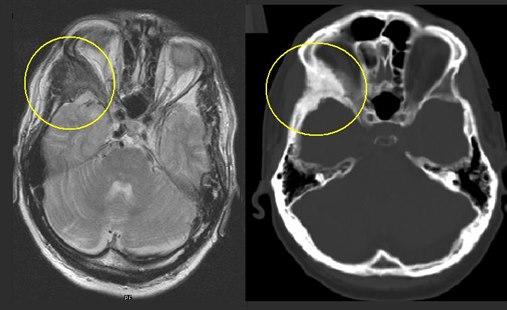

Det hyppigste stedet hvor forandringene opptrer, er i ansiktsskjelettet. Dette kan føre til synlige skjevheter eller kuler. Forandringene kan også oppstå på undersiden av skallen og kan da trykke på ryggmarg og nerver fra ryggmargen. Dersom det oppstår forandringer i legger eller lår, er det økt risiko for brudd og feilstillinger.

Diagnostikk

Forandringene kan noen ganger ses som kuler i ben - i ansiktet eller andre steder på kroppen. Andre ganger kan forandringene påvises ved røntgenundersøkelse i forbindelse med smerter eller plager. Som regel vil det være nødvendig med en vevsprøve for sikkert å fastslå diagnosen. Gentest kan også brukes.